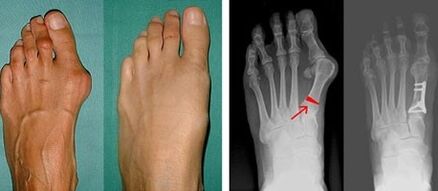

На първия етап от идентифицирането на валгус на големия и малкия пръст на крака лекарят провежда визуален преглед. По този начин определя етапа на развитие на патологията. За да се идентифицират подробни промени в ставите, се предписват рентгенови лъчи и плантография.

Ако визуалният преглед и рентгеновите лъчи не дадат резултат, тогава пациентът се насочва към плантография, за да се определи възможното плоскостъпие. Този метод включва вземане на отпечатъци от стъпалата, въз основа на които се изработват обувки или стелки с ортопедични свойства за пациента. След това на пациента се предписва подометрия. Този метод използва компютърен анализ, за да определи натиска на тежестта на човек върху краката. Резултатите от разширената диагностика са в основата на избора на метод за лечение на кривината на първия и втория пръст на крака.